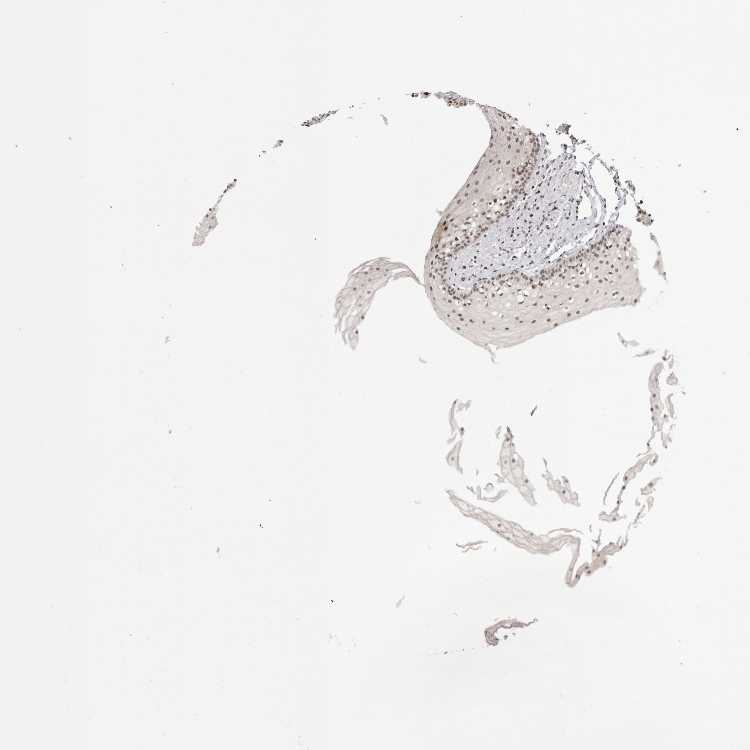

TISSUE PRIMARY DATA ORAL MUCOSA Show tissue menu

ORAL MUCOSA - Antibody stainingi

Antibody staining in the annotated cell types in the current human tissue is reported as not detected, low, medium, or high, based on conventional immunohistochemistry profiling in selected tissues. This score is based on the combination of the staining intensity and fraction of stained cells.

Each image is clickable and will lead to virtual microscopy that enables deeper exploration of all samples and also displays staining intensity scores, fraction scores and subcellular localization as well as patient and tissue information for each sample.

Antibody CAB025600Antibody CAB026380Antibody CAB079773

Squamous epithelial cells MediumMediumNot detected